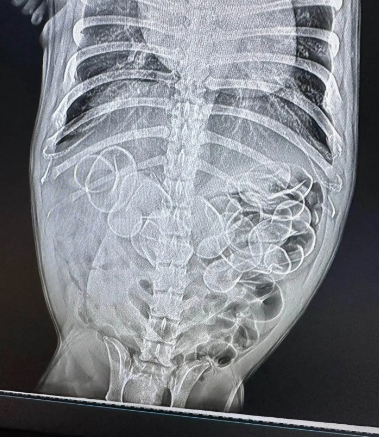

然而,当医生对狗的胃部进行X光检查时,发现它的肚子里至少有5只玩具鸭。她的狗随后被紧急送进手术室,兽医们成功取出了另外6只玩具鸭,所以总共是11只!